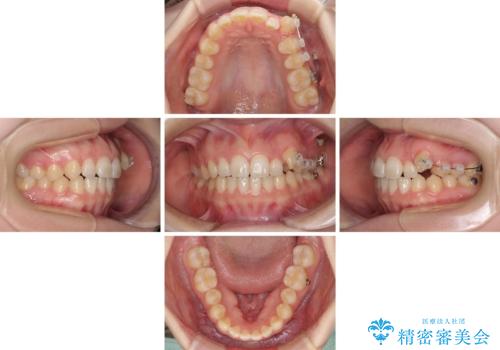

気になる残存乳歯と八重歯 ワイヤー矯正を併用したインビザライン治療

- 八重歯を気にして来院された患者様です。

八重歯のために乳歯が残存していたため、乳歯を抜去して八重歯となっている犬歯を歯列に収めることとしました。

八重歯の移動量が多くなるため、インビザラインと併用してワイヤー矯正を行い、八重歯を改善した後に、上下歯列をインビザラインで整えることとしました。

犬歯は歯根が長くて太いため移動に時間がかかる上に、周囲の歯が八重歯に寄ってきてしまうため、仕上がるまでに期間がかかりました。